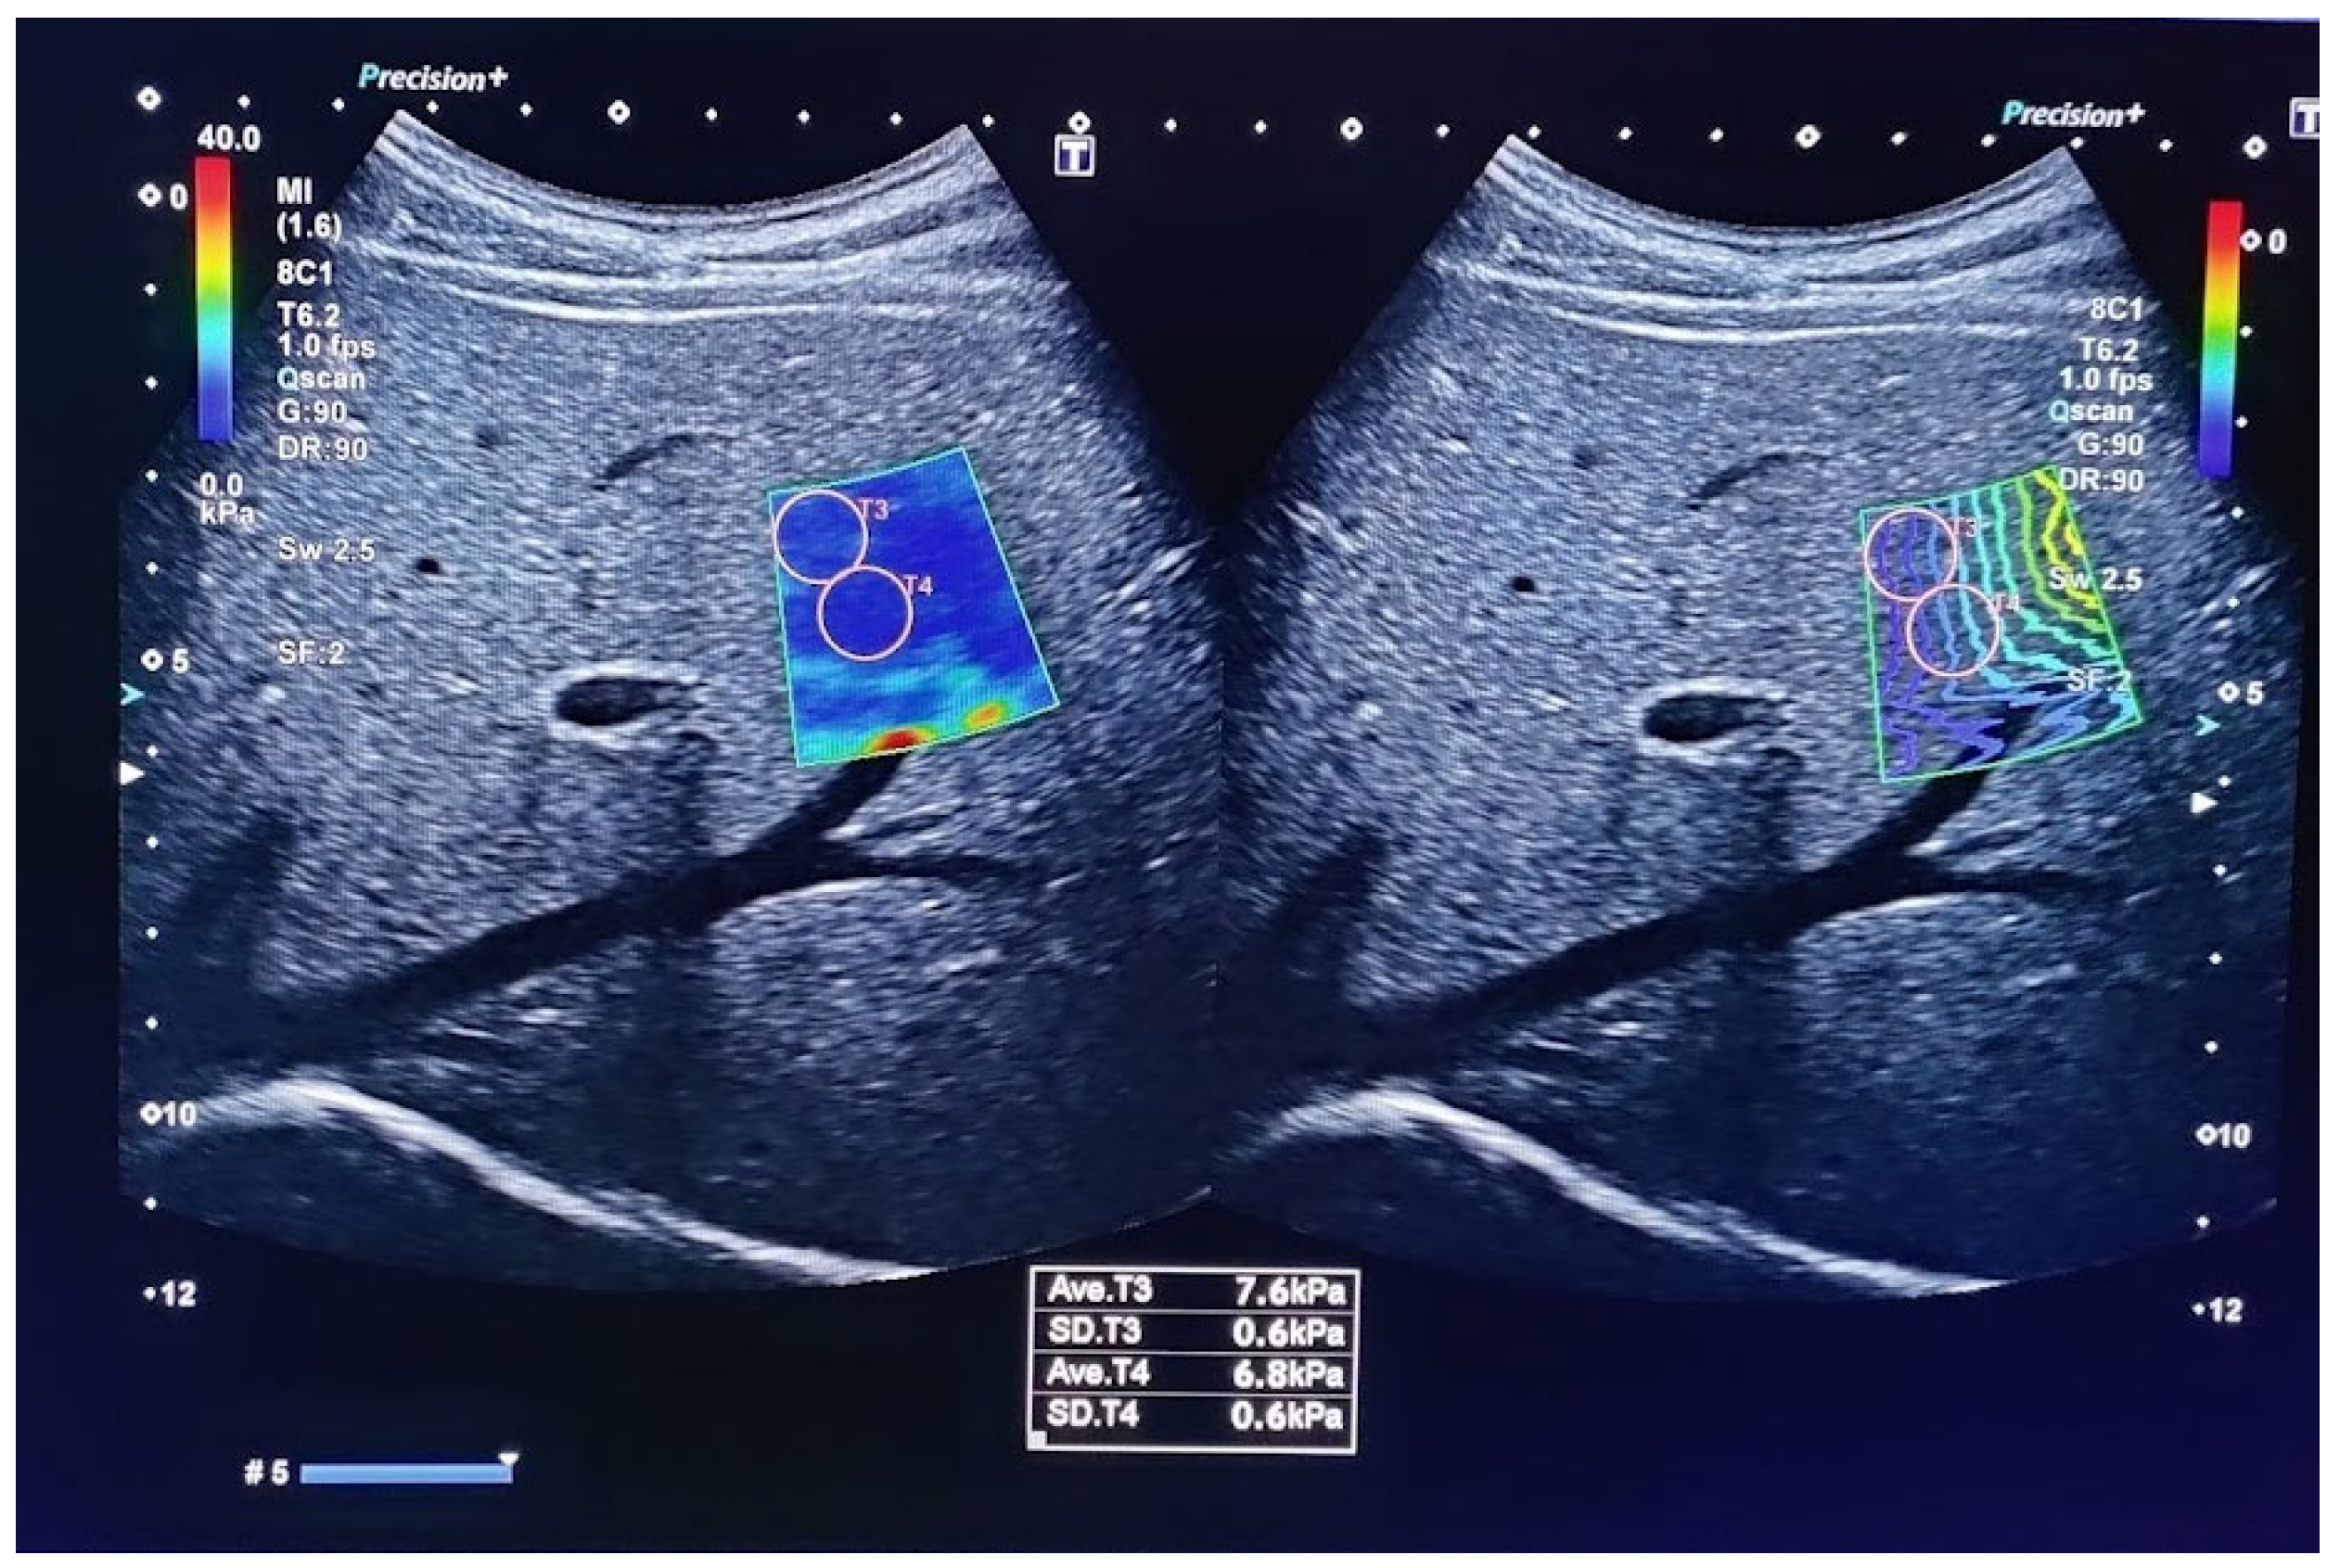

The measurement starts with a good visualization of the target organ with classical imaging. Next, the appropriate software is switched on at the desired location within the organ and points at it with the indicator, as presented in Figure 2. Several elasticity areas within the organ are measured and the mean or median value of measurement is provided using speed (m/s) and pressure (kPa) modules, both describing tissue’s elastic properties. The quality of the measurement is ensured by the manufacturer’s instructions.

Figure 2.

Ultrasound elastography using Canon aplio-a with maintenance of quality control by obtaining a standard deviation of less than 20% of the measurement as well as by maintaining an IQR/median ratio <30%.